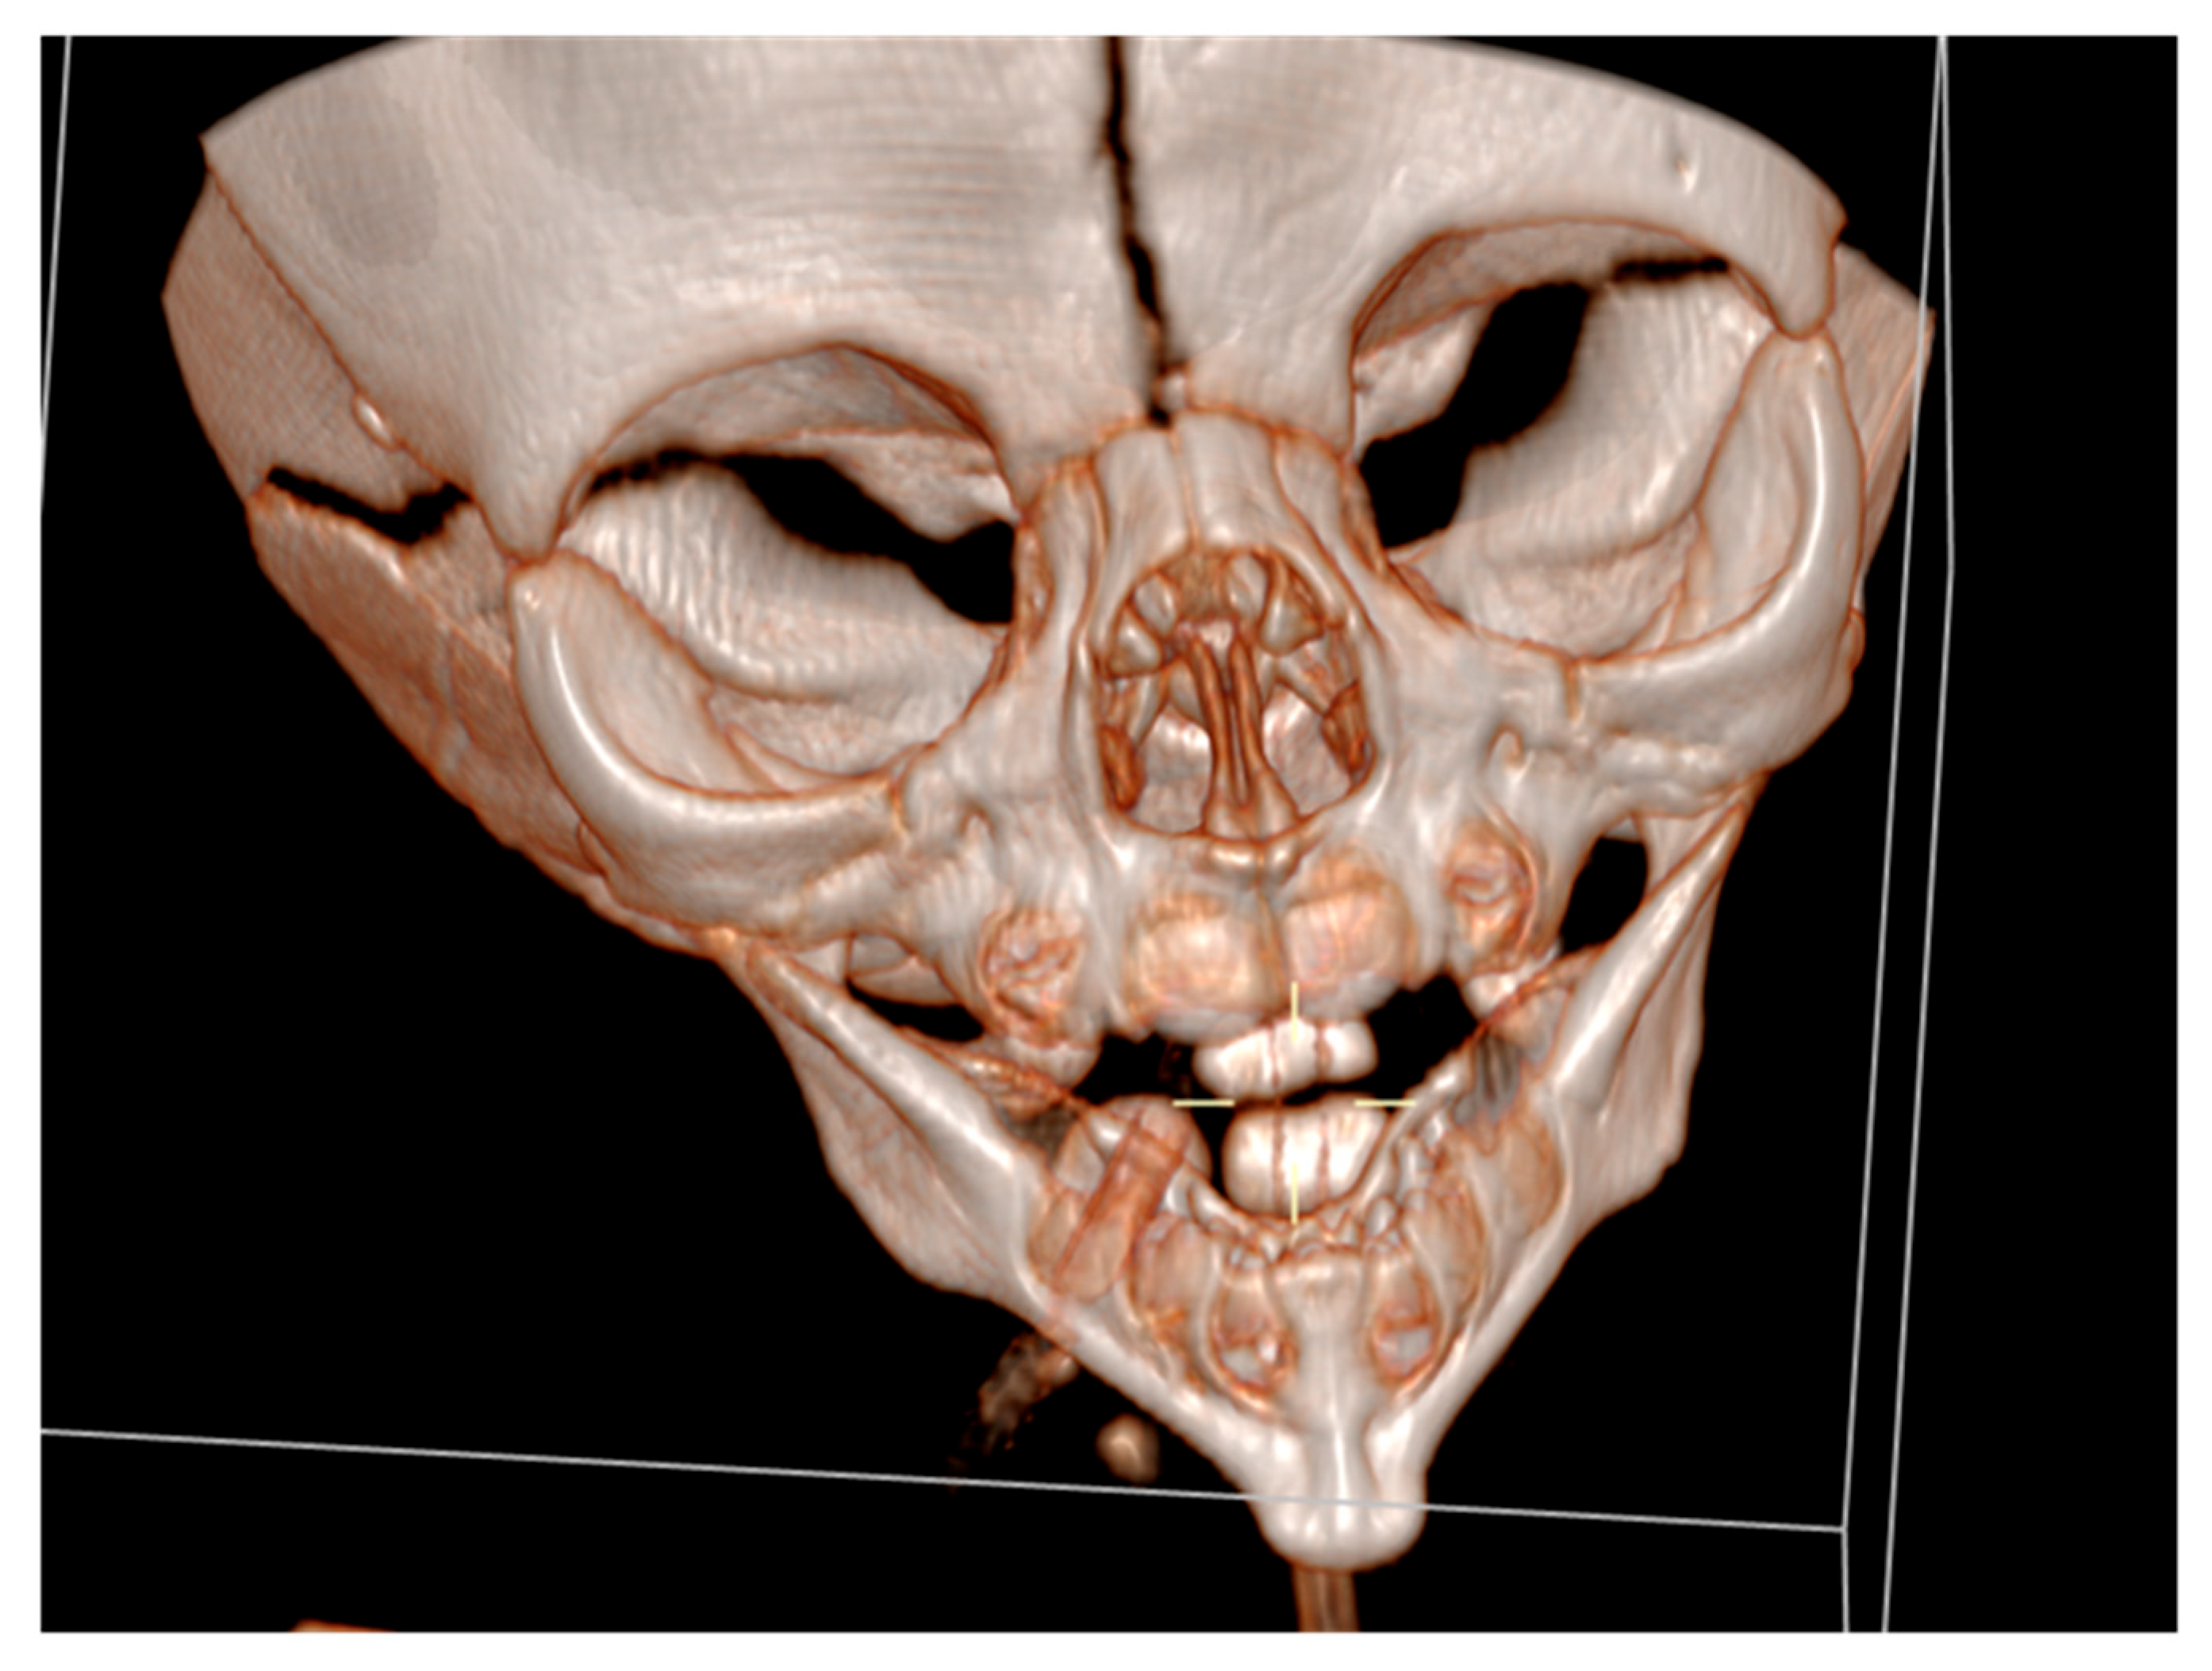

Cranial ultrasound showed no pathological findings, except for discretely hyperechoic periventricular white matter. A computed tomography of the facial region described the mandibula as hypoplastic and narrow (Figure 3).

It had underdeveloped body region and pointed chin. Only three tooth germs of the lower frontal teeth were present, specifically one lower medial incisor and two lateral incisors. Temporomandibular joints were normal (Figure 4).

Figure 3. A computed tomography of a narrow and hypoplastic mandibula.

Figure 4. Temporomandibular joints are normal.